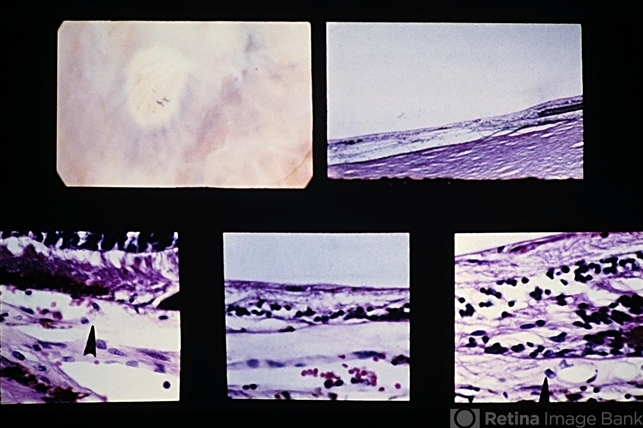

- Elschnig's spots, choroidal infarction, Bruch's membrane

- Elschnig spot. Localized choroidal infarction with loss of choriocapillaris, RPE, and outer layers of the retina. The thinned inner nuclear layer of the retina rests against Bruch's membrane. At the anterior margin (lower left view) there is an abrupt transition (arrow) between the normal area (left) where the choriocapillaris and RPE are intact and the area of post-ischemic atrophy of the structures (right). A similar but reversed configuration is observed at the posterior margin (lower right view).